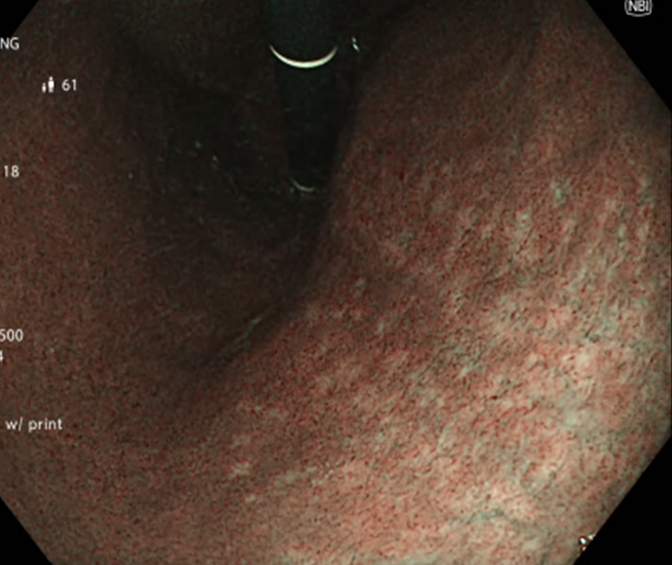

Kết quả nội soi đại tràng: có 3 polyp đại tràng (Paris Is, Kudo IIIL) (đã được cắt polyp qua nội soi), đại tràng sigmoid đã cắt một phần, tổn thương lồi đại trực tràng dạng polyp không cuống, ranh giới rõ, bề mặt màu hồng, có nhiều polyp có lớp nhầy ở trên bề mặt và thấy có hình ảnh da gà xung quanh tổn thương. Trên hình ảnh M-NBI thấy các tổn thương có các tuyến giãn nhẹ nhưng còn đều, mạch máu giãn nhẹ, chưa có biến đổi hình dạng --> đã tiến hành sinh thiết

Hình 2: Hình ảnh nội soi đại tràng

Tổn thương trên nội soi là hình ảnh các tổn thương lồi tại đại trực tràng dạng polyp không cuống, ranh giới rõ, bề mặt màu hồng, có nhiều polyp có lớp nhầy ở trên bề mặt. Chúng tôi nghĩ đến đây là hình ảnh của đa polyp mũ đại tràng mặc dù kết quả mô bệnh học chỉ kết luận là tổn thương viêm trợt mạn tính đang hoạt động, tạo hình ảnh giả polyp. Do trước đó cô ấy đã trải qua nhiều phương pháp điều trị theo hướng viêm ruột như kháng sinh Tinidazol, Levofloxacin, mesalazine… nhưng tình trạng đại tiện nhiều lần không được cải thiện, cùng với đó chúng tôi ghi nhận thấy có sự hiện diện của vi khuẩn H.pylori ở dạ dày. Vì vậy chúng tôi đã quyết định điều trị diệt trừ vi khuẩn H.pylori bằng phác đồ 4 thuốc: Tetracyclin 2g/ngày, Tinidazol 1,5g/ngày, Esomeprazol 80 mg/ngày, Bismuth 480 mg/ngày, thời gian điều trị là 2 tuần.